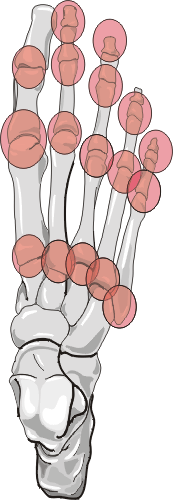

| Joint | Frequency |

|

| 1st interphalangeal | +++ |

| 2nd - 5th interphalangeal | + | |

| 1st Metatarsophalangeal | +++ | |

| 2nd-5th Metatarsophalangeal | ++ |

| Tarsometatarsal | - |

| Chopart | - |